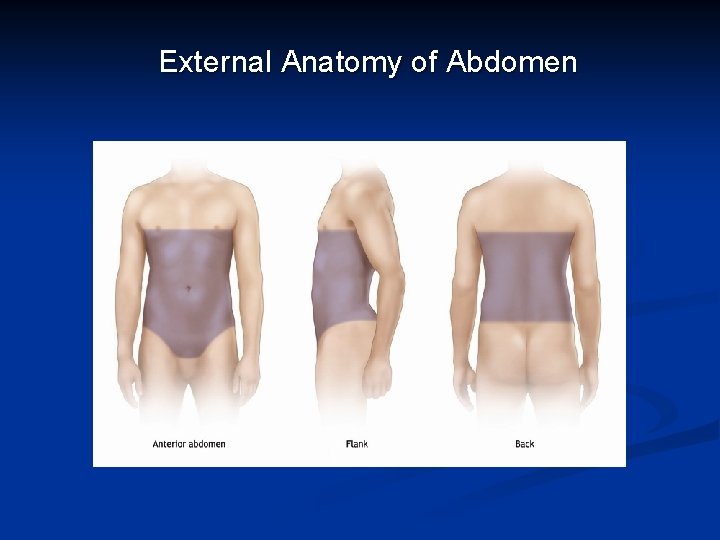

External Anatomy of Abdomen